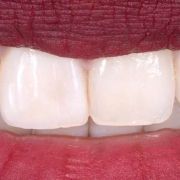

I used one hue (B), three opacities (Enam.,Body, Dent.) and two different chroma of the same hue (B1,B2).

Different posing revealing different natural light reflections on the tooth!